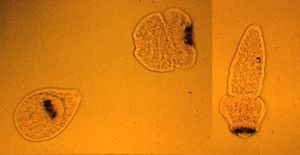

'''감염증의 병원체 전자현미경 사진 예'''